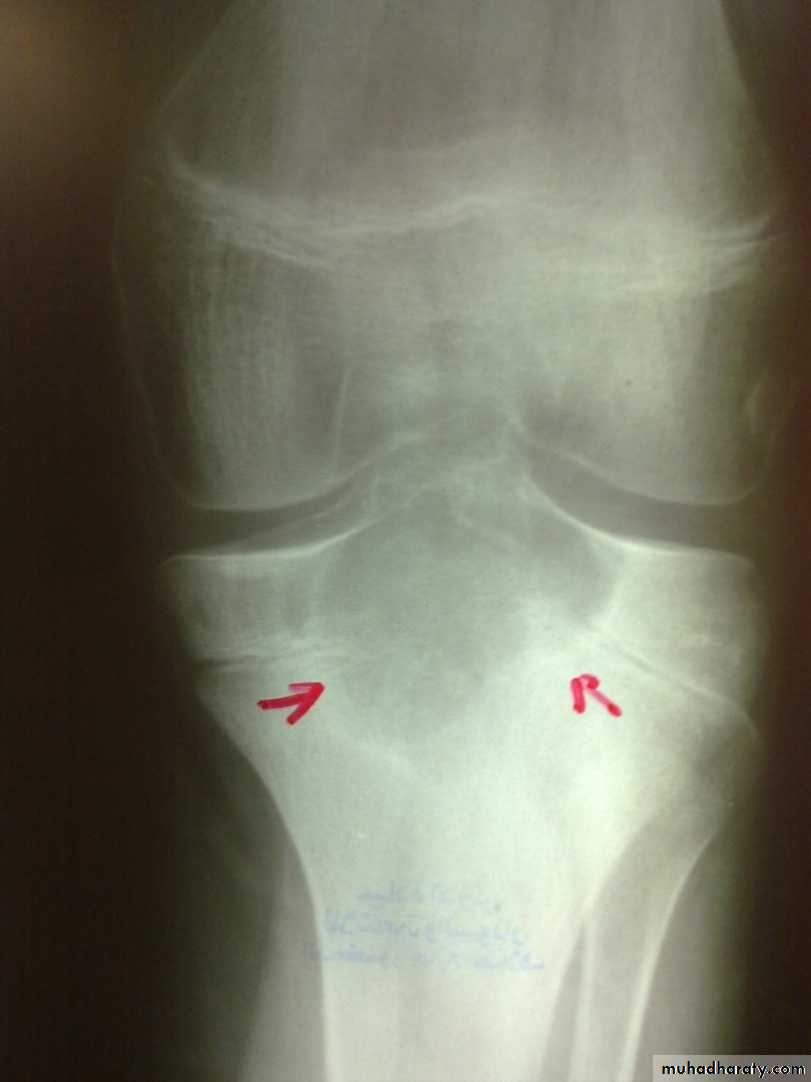

Radiological features

early changes:

Soft tissue swelling, Periarticular osteoporosis

Loclized osteoprosis (Bone ends ‘washed – out’ or localized decalcification ).

Narrowing and irregularity of the articular ends.

Late changes:

Erosions of the subarticular cartilage.

cystic changes appeared.